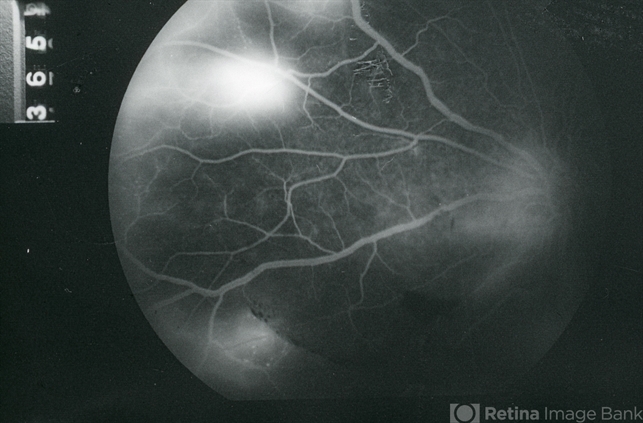

- EALES DISEASE

- Eales disease, neovascularization elsewhere (NVE), fluorescein angiogram (FA), FA late phase, FA late phase leakage

- Late-phase (5 minutes) fluorescein angiogram image of the nasal mid-periphery of the left eye of a 23-year-old Vietnamese female with Eales Disease showing multiple areas of NVE and some disc leakage.